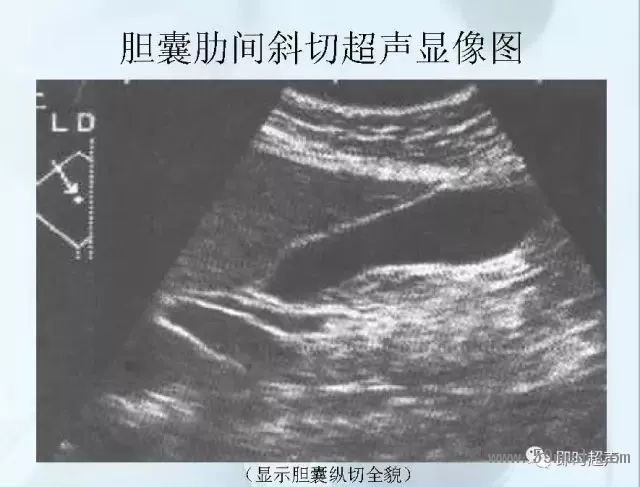

![]() ![]() ![]() ![]() ![]() ![]() ![]() ![]() ![]() ![]() ![]() ![]() ![]() ![]() ![]() ![]() ![]() ![]() ![]() ![]() ![]() ![]() ![]() ![]() ![]() ![]() ![]() ![]() ![]() ![]() ![]() ![]() ![]() ![]() ![]() ![]() ![]() 【注:本文來源于即時超聲,版權(quán)歸原作者所有,如有侵權(quán) 請聯(lián)系 速刪】 =========================== 【閱精彩*悅分享】隨手點擊轉(zhuǎn)至朋友圈,與大家一起分享精彩資訊!當(dāng)然您也可以通過以下方式找到我,與您共同分享藍(lán)韻影像超聲的更多精彩!微信號:landultrasound 電話:+86-0755-66869896 24小時客服熱線:400-888-6452